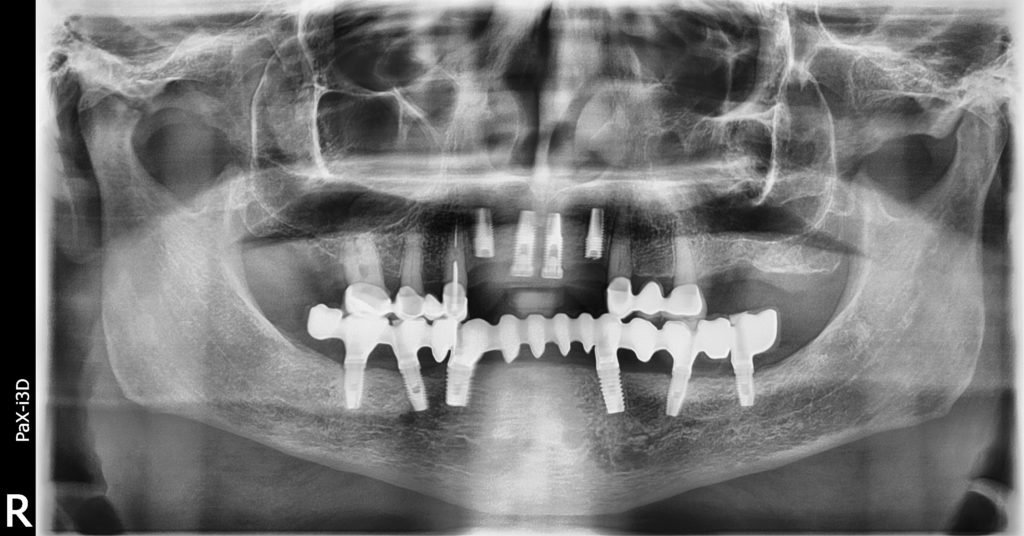

Buenas tardes Me llega este paciente de idental y soy incapaz de reconocer los implantes agradecería ayuda para identificarlos Muchísimas gracias

El paciente acude con fractura de los implantes 1.2 y 2.2. Necesitaríamos saber marca implante y conexión de los implantes 1.1 y 2.1. Saludos y gracias.

Hola , no sabemos que implante son el de 24 y 25 , si me podeis ayudar gracias.